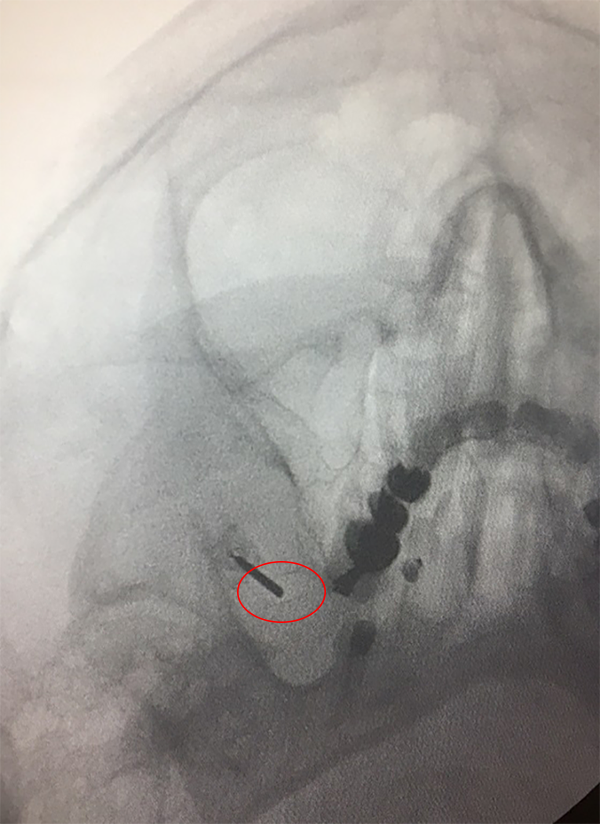

Figura 1: Identificación del Foramen Oval.

En todos los casos se colocó el paciente sobre la camilla de cirugía apoyando la cabeza sobre un cabezal radio lucido, se giró la cabeza levemente 20° aproximadamente hacia el lado opuesto a la neuralgia, allí se marcó luego los puntos de Hartel: un punto inmediatamente medial y debajo de la pupila, un punto a 3 cm delante del conducto auditivo externo para obtener la trayectoria rostral/caudal y medial/lateral respectivamente. El último punto se ubicó a 2.5 cm lateral a la comisura labial. Se realizó radioscopia para objetivar el foramen oval homolateral al dolor (fig. 1). Se procedió a realizar sedo analgesia en el paciente con propofol. Bajo radioscopia y previo campo estéril se realizó la punción, a 2.5 cm en sentido lateral a la comisura labial intentando introducir la cánula para termocoagulación por radiofrecuencia de 10 cm con punta recta de 5 mm por el foramen oval en su porción medial, una vez canulado el foramen y dentro de la cisterna trigeminal se objetivó la mayoría de las veces, no siempre, la salida de líquido céfalo raquídeo (LCR) (fig. 2). Se realizó radioscopia en sentido lateral tomando como referencia el piso de la silla turca y el clivus a 5 mm, 10 mm o 15 mm según cual rama se quiso estimular, rama V1, V2 o V3 respectivamente (fig. 3). Se conectó la aguja al electrodo de radiofrecuencia previamente conectado al dispositivo generador de radiofrecuencia (FL Fisher Neuro N50) (fig. 4), para estimular la rama motora a 5 Hz, una vez despierto el paciente se procedió a realizar estimulación a 50 Hz para objetivar el patrón de dolor habitual.

Figura 1: Identificación del Foramen Oval.